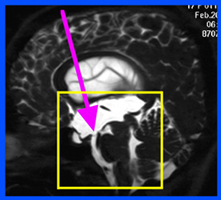

水頭症

水頭症とは病態を総称したものであり、小児脳神経外科領域で対応する水頭症は図(胎児水頭症ガイドラインより)の通りさまざまな原因によって発症します。そのために発症による日常生活動作の状態もさまざまです。

2つの画像のキャプション:胎児水頭症診断と治療ガイドライン(2010)より抜粋

水頭症はどのような状態であっても発症しているこどもの発達の足かせとなるため、治療が必要です。現在水頭症の治療には2つの方法があります。ひとつは「シャント術」と言われる短絡術、もうひとつは神経内視鏡を用いた「第三脳室底開窓術」です。